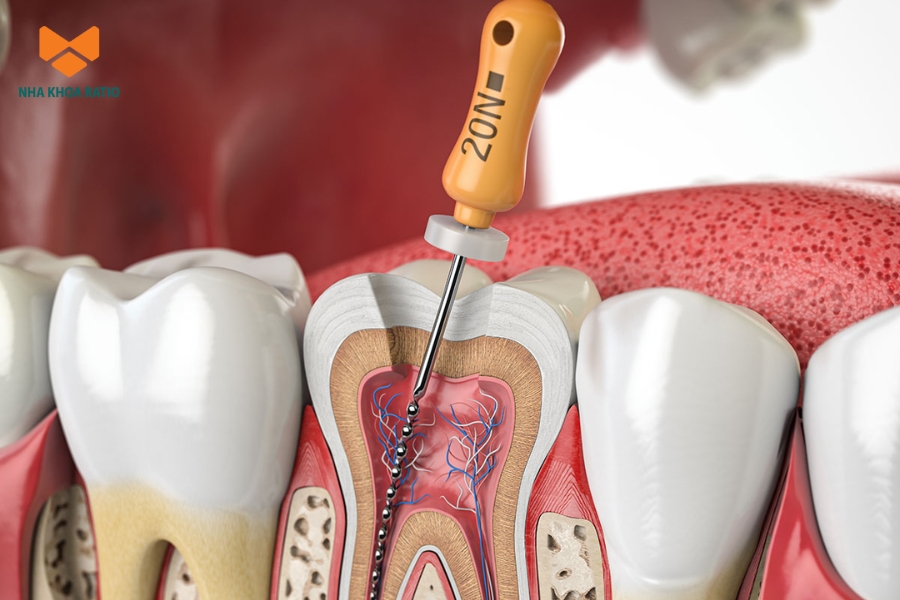

Điều trị tủy răng hay điều trị nội nha là thủ thuật nha khoa nhằm loại bỏ phần tủy bị viêm hoặc nhiễm trùng bên trong răng. Sau khi lấy sạch mô tủy, bác sĩ sẽ tiến hành làm sạch và khử trùng để loại bỏ hoàn toàn vi khuẩn còn sót lại.

Mục đích của quy trình này là ngăn chặn nhiễm trùng lan rộng, đồng thời duy trì cấu trúc răng còn lại. Khi tủy đã được lấy sạch, răng sẽ không còn đau và chức năng nhai được duy trì ổn định.

- Bước 4: Thực hiện điều trị tủy răng

Bác sĩ dùng mũi khoan chuyên dụng để tiếp cận tủy răng, loại bỏ phần tủy bị nhiễm trùng. Sau đó làm sạch và khử trùng bên trong răng.

- Bước 5: Trám bít ống tủy

Sau khi phần tủy viêm hoặc tủy hoại tử được lấy sạch, bác sĩ sẽ tiến hành trám bít ống tủy. Vật liệu thường dùng là nhựa nha khoa chuyên dụng, được đặt vào toàn bộ chiều dài ống tủy để niêm kín hoàn toàn đường thông vừa tạo ra.